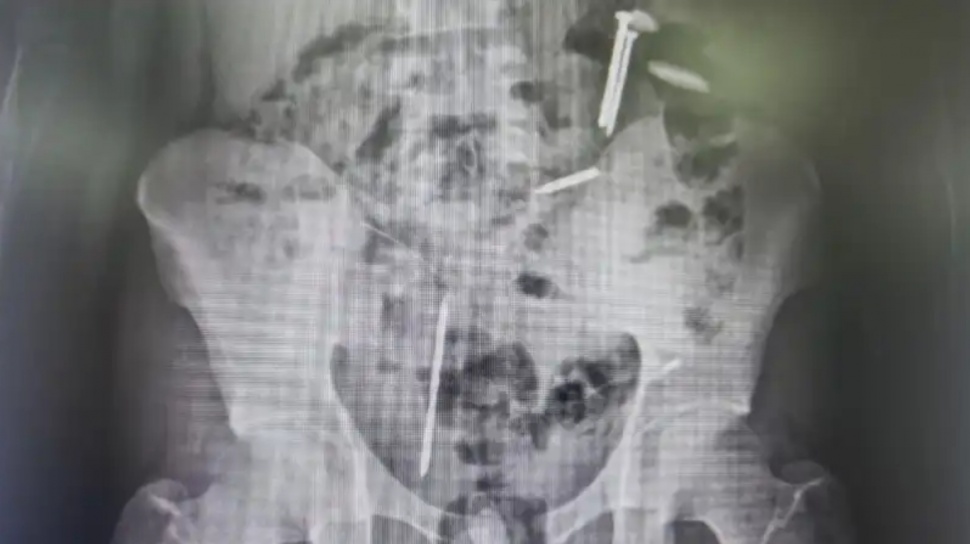

SuaraJatim.id - Dua buah paku dan tiga benda asing yang belum teridentifikasi ditemukan di dalam tubuh Mohamad Vemas Agung (23), warga Dusun Lengkong, Desa Wonosari, Kecamatan Puger, Kabupaten Jember, Jawa Timur, yang sempat dipasung karena gangguan jiwa.

Keberadaan benda-benda asing ini terungkap dari hasil foto ronsen dan cek kesehatan sebelum Vemas menjalani pemeriksaan kejiwaan di Rumah Sakit Jiwa (RSJ) Lawang, Malang, oleh Unit Pelaksana Teknis Lingkungan Pondok Sosial Dinas Sosial Jember dan relawan Ben Seromben Indonesia.

"Ada hitam-hitam yang kami tidak tahu itu apa, apakah gumpalan darah atau apa. Kami tidak bisa memastikan," kata Kepala UPT Liposos Dinas Sosial Jember, Roni Effendi, Rabu (8/4/2026) dikutip dari beritajatim.com--jaringan Suara.com.

Pihak RSJ Lawang menyarankan agar persoalan ini diselesaikan dulu sebelum menjalani rawat kejiawaan.

"Karena itu butuh tindakan besar, misalkan terjadi apa-apa, kami langsung menghubungi keluarga bersangkutan. Ayah dan kakaknya meluncur ke RS Jiwa Lawang. Tindakan (operasi) besar ini butuh statement orang tua," kata Roni.

Dari penjelasan keluarga diketahui bahwa Vemas memang sembarangan menelan benda-benda asing sejak lama. “Namun pihak keluarga tidak tahu apa saja yang dimakan,” kata Roni.